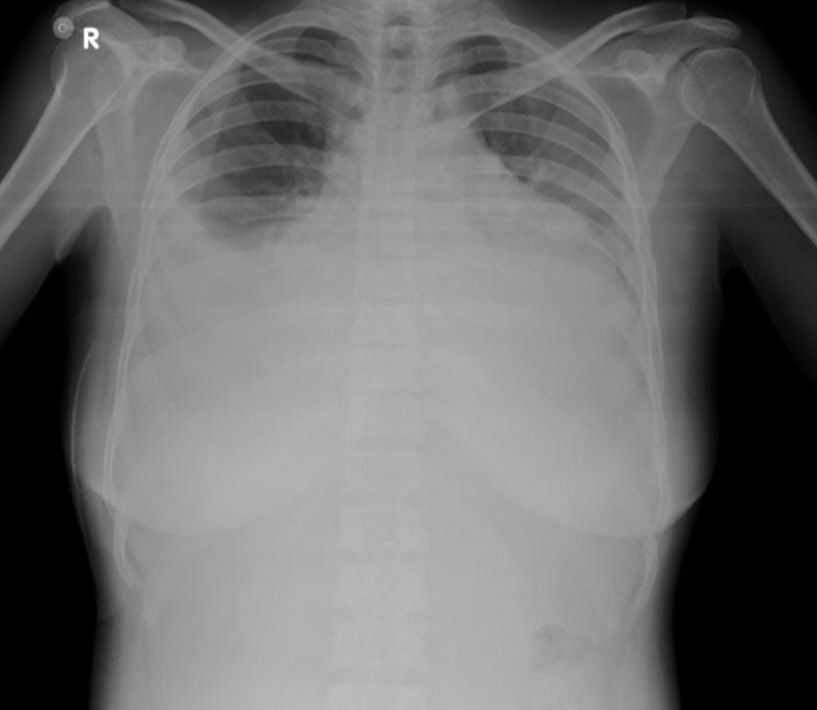

Tactile  vocal fremitus - reduced on both sides  in infra axillary and infra scapular region

PERCUSSION- Dull on both the sides

AUSCULTATION -  Decreased respiratory sounds on both the sides.